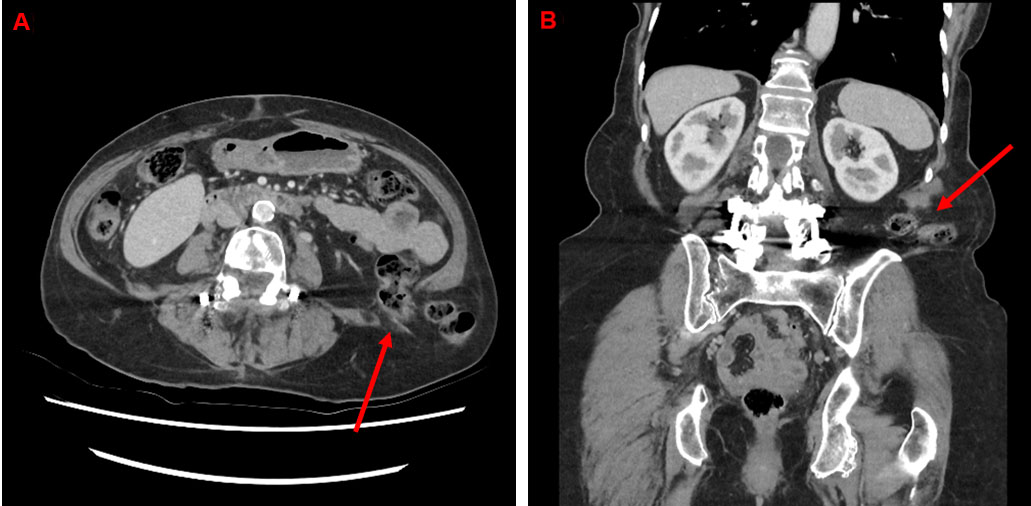

On examination, there was a tender, right lumbar mass superior to the iliac spine, likely a lumbar hernia secondary to traumatic injury with rupture of muscle and a subsequent hematoma. Computed tomography abdomen and pelvis demonstrated a right posterolateral abdominal wall hernia measuring approximately 55 mm anteroposteriorly and 48 mm craniocaudally. There was herniation of omental fat and appendix through this defect (Figure 1A and Figure 1B). On further review, the patient was consented and booked for an open repair of the hernia and placement of a sublay mesh due to underlying respiratory illness and immunocompromised state.

On clinical examination, the patient had a completely reducible left lumbar hernia. The diagnosis was subsequently confirmed on CT abdomen, pelvis demonstrating a left sided inferior lumbar hernia measuring 41 mm × 33 mm containing unobstructed descending colon and omentum (Figure 5A and Figure 5B). The patient was therefore booked for an urgent repair due to high risk of strangulation and subsequent morbidity.

Figure 1: Case 1—(A) axial, (B) coronal CT abdomen and pelvis with intravenous (IV) contrast demonstrating a right lumbar hernia (red arrow—B) with omental fat and appendix (red arrow—A) through the hernia defect.

Figure 5: Case 2—(A) axial, (B) coronal CT abdomen and pelvis with intravenous (IV) contrast demonstrating a left-sided inferior lumbar hernia measuring 41 mm × 33 mm containing unobstructed descending colon and omentum (red arrows).